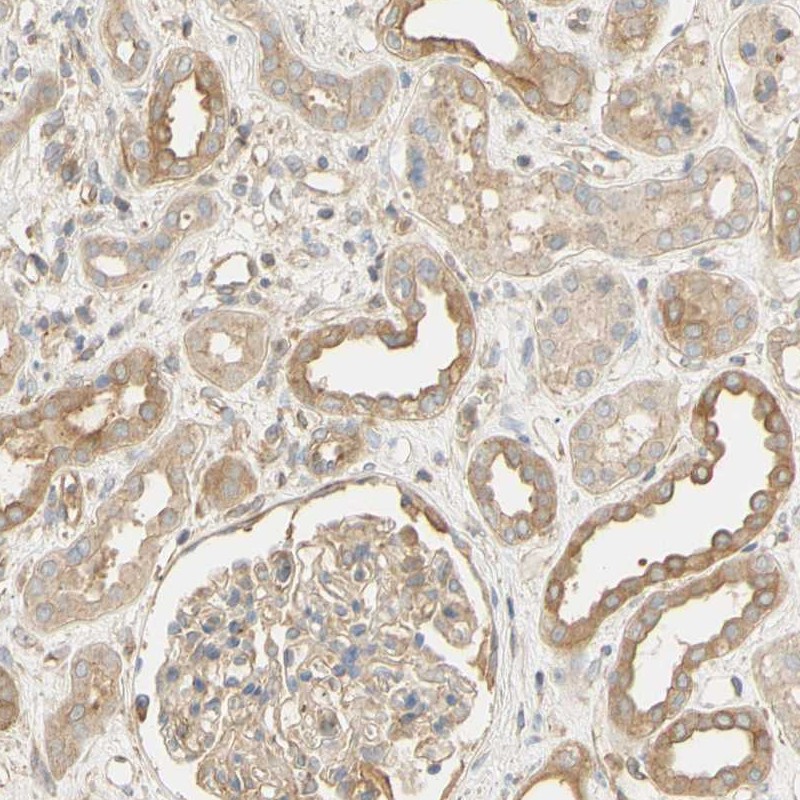

Immunohistochemical staining of human kidney shows moderate cytoplasmic positivity in cells in tubules.